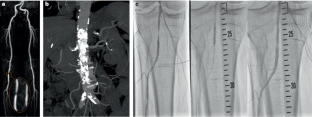

Collins, R. et al. A systematic review of duplex ultrasound, magnetic resonance angiography and computed tomography angiography for the diagnosis and assessment of symptomatic, lower limb peripheral arterial disease. Health Technol. Assess. 11, 1–184 (2007).

Met, R., Bipat, S., Legemate, D. A., Reekers, J. A. & Koelemay, M. J. W. Diagnostic performance of computed tomography angiography in peripheral arterial disease. JAMA 301, 415 (2009). The role of CTA in PAD.

Menke, J. Meta-analysis: accuracy of contrast-enhanced magnetic resonance angiography for assessing steno-occlusions in peripheral arterial disease. Ann. Intern. Med. 153, 325 (2010).